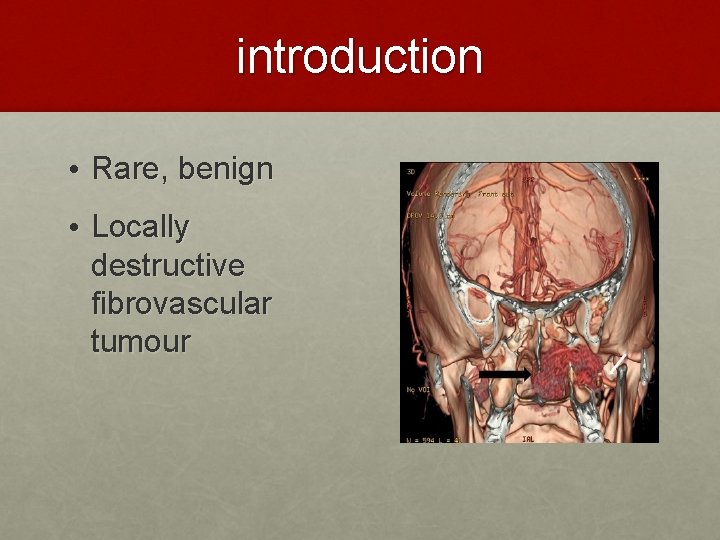

introduction • Rare, benign • Locally destructive fibrovascular tumour